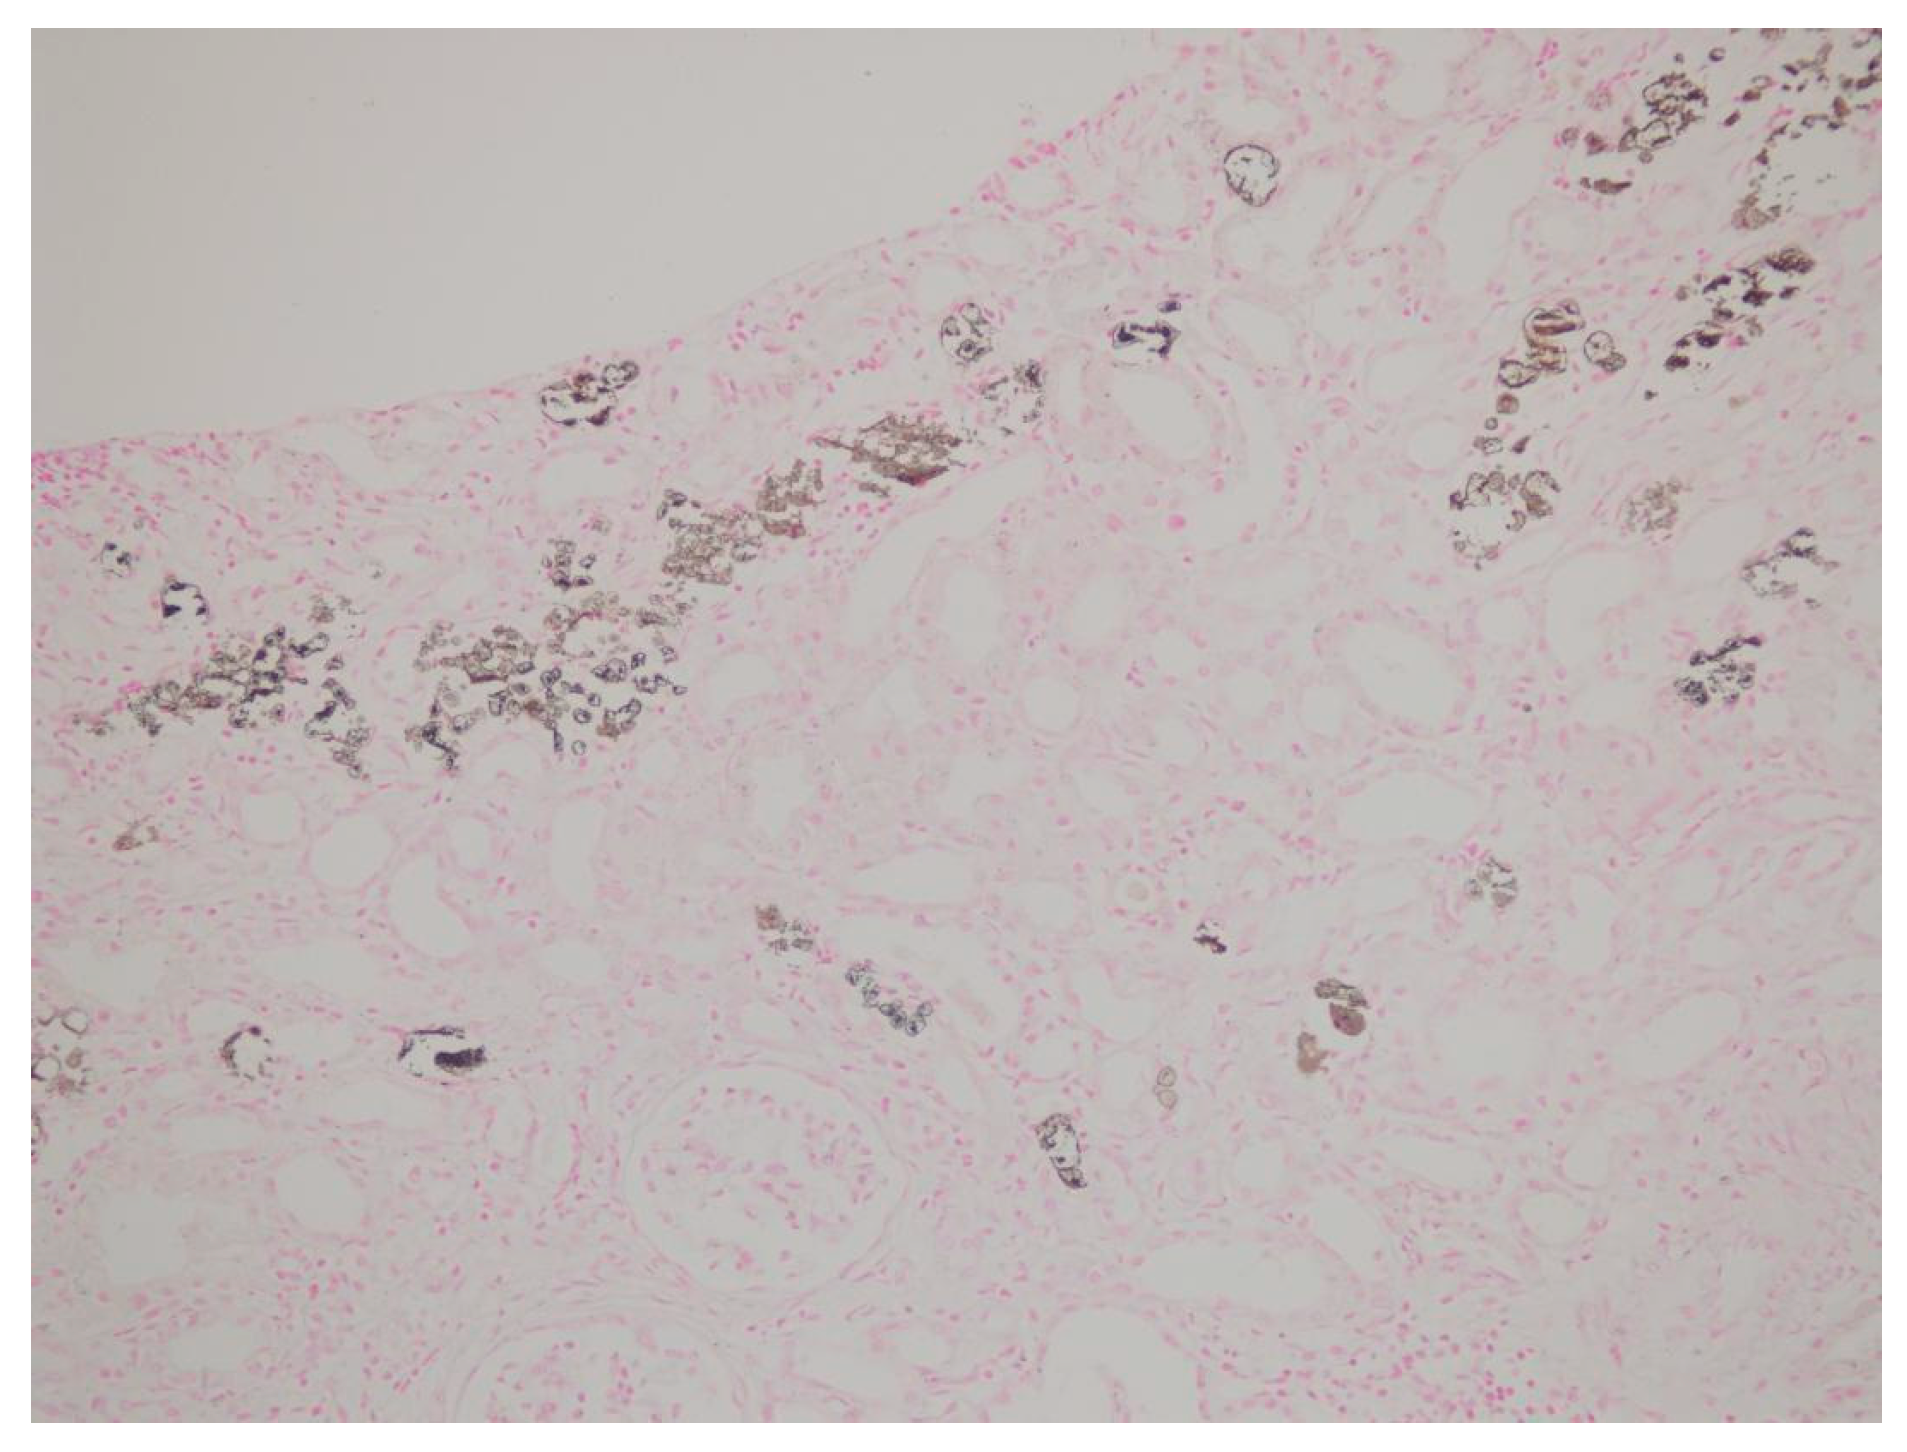

| Tubulointerstitial deposition | + | + | + | + | + | + | + | + | + |

| von Kossa staining | + | + | + | + | + | + | + | + | + |